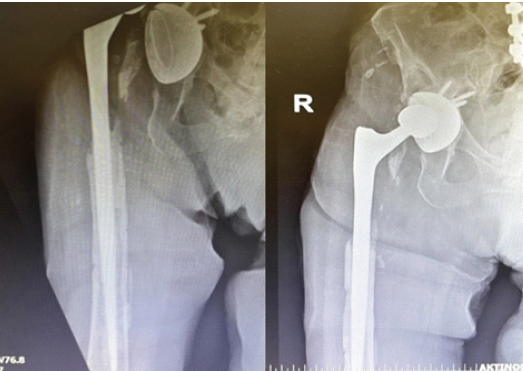

On the 30th post-operative day, the patient underwent a second surgical debridement through the previous incision and approach, which included removal of the remaining cerclage wires and retrieval of bone cement specimens for sonication. Following infectious disease consultation, the antimicrobial regimen was adjusted to meropenem, caspofungin (70 mg/day intravenously), and daptomycin (700 mg/day intravenously), pending the results of the repeat microbiological cultures. The subsequent post-operative course was uneventful. Sonication of the retrieved cement yielded C. albicans. Meropenem was administered for a total of 3 weeks for the treatment of bacteremia, whereas caspofungin and daptomycin were continued intravenously. At 3 weeks postoperatively, the wound had healed adequately, sutures were removed, and the patient was discharged in good general condition. She was prescribed oral trimethoprim-sulfamethoxazole (960 mg twice daily) and fluconazole (200 mg twice daily) for prolonged suppressive therapy. Twenty days after discharge, the patient was readmitted due to a new prosthetic hip dislocation, which was managed with closed reduction in the emergency department. On readmission, her CRP was 1.06 mg/dL, without clinical or laboratory evidence of recurrent infection. Given the absence of systemic inflammatory response, a conservative approach was adopted, and she was discharged after a short hospital stay with instructions to continue oral fluconazole and trimethoprim–sulfamethoxazole (Fig. 2).

Figure 2: Anteroposterior radiograph demonstrating dislocation of a revision total hip arthroplasty, treated with closed reduction during ongoing antibiotic and antifungal therapy.